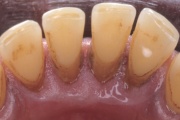

- puudulik suuhügieen (5)

- igemepealne hambakivi (5)

- igemealune hambakivi (4)